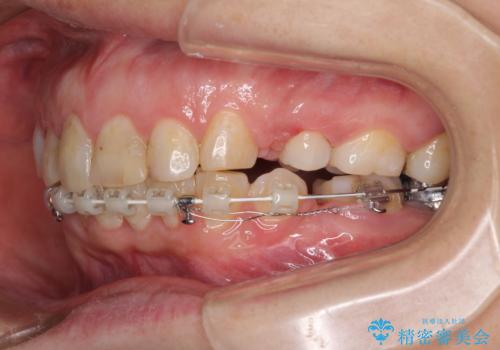

- 前歯のデコボコと前方に斜めに飛び出した前歯を気にして来院された患者様です。

口元の突出感はあまり気になっていませんでしたが、上下の前歯の前後差が大きかったため、上顎左右の第一小臼歯を抜歯し、上顎が裏側装置であるハーフリンガルにて矯正治療を行うこととしました。

咬合力が非常に強く、スペースがなかなか閉じなかったことと、上下の正中が著しくずれてきてしまったため、下顎左側小臼歯を途中抜歯することとなりました。